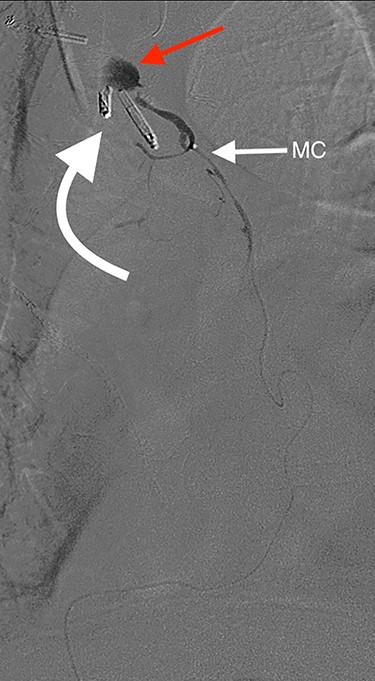

Angiography showing extravasation at the anastomosis. Curved arrow = OG anastomosis; Red arrow = contrast extravasation; Arrow MC = microcatheter.

Eight days later, he represented with an upper gastrointestinal bleed with massive haematemesis requiring immediate intubation for airway protection. Computer tomography angiography was unremarkable and an emergency gastroscopy revealed an extensive amount of blood and clot in the oesophagus and gastric conduit (limiting the view), but no active bleeding point. Conservative treatment in the Intensive Care Unit (ICU) with blood transfusion, proton pump inhibitors and life support were implemented. Another large bleed occurred 2 days later and a repeat gastroscopy revealed a non-bleeding visible vessel at the OG anastomosis and a haemostatic clip was applied. However, over the next 10 days, the patient remained blood transfusion dependent and had two further endoscopies. The first was unremarkable, but the second endoscopy re-demonstrated the luminal vessel at the OG anastomosis, with no evidence of the previously placed clip. This was felt to be the cause of his intermittent and problematic bleeding, so another haemostatic clip was attempted, resulting in pulsatile, moderate volume arterial bleeding. The procedure was abandoned and the patient transported immediately to the Interventional Radiology Suite. Right femoral access was obtained and angiography performed. The thoracic aorta was normal, so the celiac trunk was cannulated and angiography of the right gastro-epiploic artery performed (Fig. 1), revealing active extravasation of contrast at the OG anastomosis as shown in Fig. 2. A microcatheter was advanced along the length of the right gastro-epiploic artery to the OG anastomosis and coil embolization was performed (Fig. 3). Care had to be taken to ensure that the embolization was as distal as possible to limit the risk of ischaemic complications. The patient required lengthy ongoing care in the ICU for organ dysfunction but remained hemodynamically stable after embolization without evidence of conduit ischaemia. His hospital stay was obviously lengthy, but he was ultimately transferred to a rehabilitation unit.

Oesophagectomy is a major operation with significant perioperative morbidity. Respiratory and cardiac complications, along with gastric conduit ischemia and anastomotic leak, tend to dominate [3]. However, bleeding complications apart from those occurring intra-operatively are rarely reported [1, 2]. We present a unique case of an anastomotic bleed from a terminal branch of the gastro-epiploic vascular arcade. While the origin of this vascular arcade is a defined vessel (right gastric-epiploic artery) visible to the naked eye, the terminal portion is comprised of submucosal arterioles and capillaries and often devoid of a visible vessel [4]. However, as shown in Fig. 1, vascular supply to the terminal portion of the gastric conduit is present and can be abundant. The bleeding in this case likely occurred from incorporation in the anastomosis of either an invisible submucosal arteriole or the terminal portion of the right gastro-epiploic artery hidden within omental tissue. It is our standard practise to construct the OG anastomosis with the EEA circular stapler. It is common surgical knowledge that the oesophageal wall is thick [5] and has been our practise to use the 4.8-mm EEA staple height. There are several descriptions in the literature about this anastomotic technique and most recommend this staple height [6–8]. However, we believe that the higher staple height may have contributed to the bleeding issue in this case as there may have been insufficient compression of a submucosal arteriole. While it is impossible to be certain if a lower staple height would have prevented this situation, this case has resulted in our change to use the 3.5-mm EEA. In addition to this, we have become more meticulous in ensuring that the portion of the great curvature to be used for the anastomosis is cleared of excessive omental tissue to be sure no visible vessel is present that may get caught in the anastomosis.